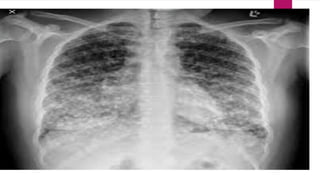

Tubercle formed in pulmonary

tuberculosis

 As these lesions heal they become calcified and

leave a scar that becomes visible on the x-ray of the

lungs as the defined shadow they are called as

Ghon complexes.